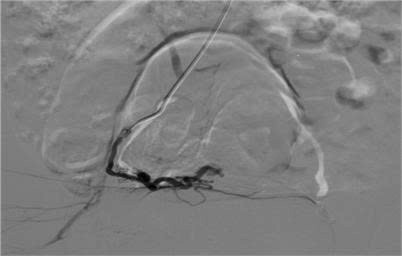

Bệnh nhân ngay lập tức được chuyển sang hội chẩn tại Trung tâm Can thiệp mạch – Bệnh viện Việt Đức. Kết quả chụp mạch số hóa xóa nền (DSA) xác nhận chẩn đoán ban đầu chính xác, đồng thời tiến hành nút mạch tại các vùng mạch máu tổn thương.

Sau can thiệp, tình trạng chảy máu âm đạo chấm dứt, bệnh nhân nhanh chóng ổn định và được chuyển về Bệnh viện Phụ sản Trung ương theo dõi, sau đó ra viện trong tình trạng khỏe mạnh, tái khám định kỳ ổn định.

Siêu âm là một phương tiện đầu tay hiệu quả để chẩn đoán cũng như tiên lượng các tổn thương AVM. Chụp mạch máu số hóa xóa nền (DSA) là tiêu chuẩn vàng trong chẩn đoán AVM và đồng thời việc nút chọn lọc các mạch máu tổn thương là biện pháp điều trị hiệu quả cho bệnh nhân.